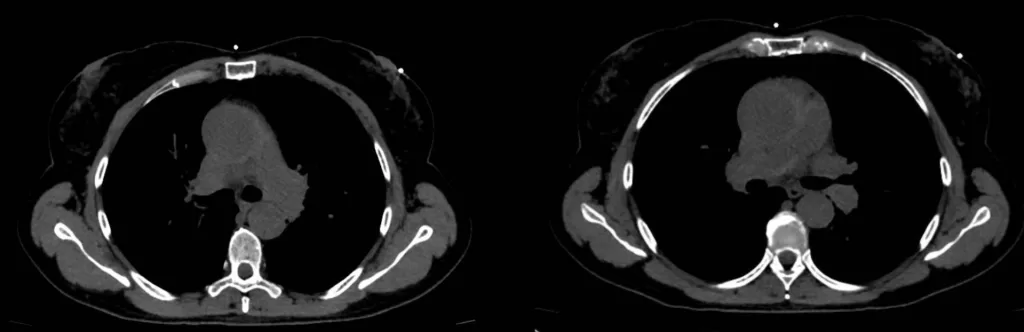

Tomografia Computadorizada de Tórax Sem Contraste

Janela mediastinal